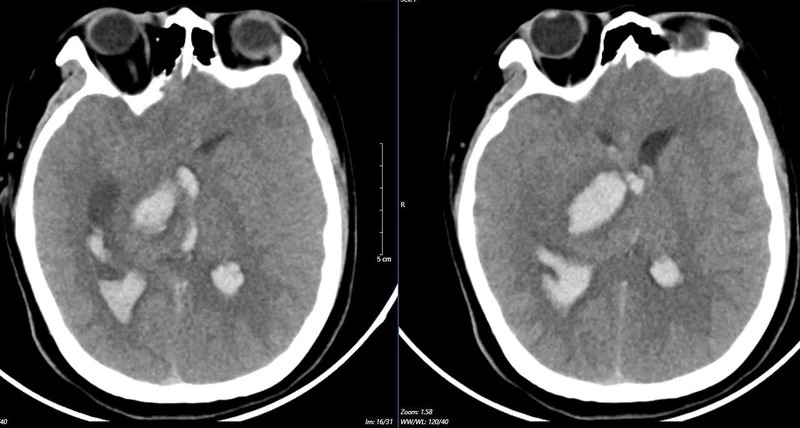

Kết quả chụp lại phim MSCT mạch não chảy máu não đồi thị - não thất do vỡ khối AVM của bệnh nhân 15 tuổi. |

Bệnh nhân vào Trung tâm Đột quỵ, Bệnh viện Bạch Mai trong tình trạng hôn mê sâu, Glasgow 5 điểm, thở máy, giãn đồng tử bên phải. Kết quả chụp lại phim MSCT mạch não chảy máu não đồi thị - não thất do vỡ khối AVM (dị dạng thông động- tĩnh mạch não) biến chứng giãn não thất cấp, rối loạn thân nhiệt, sốt cao liên tục 39-40 độ C.